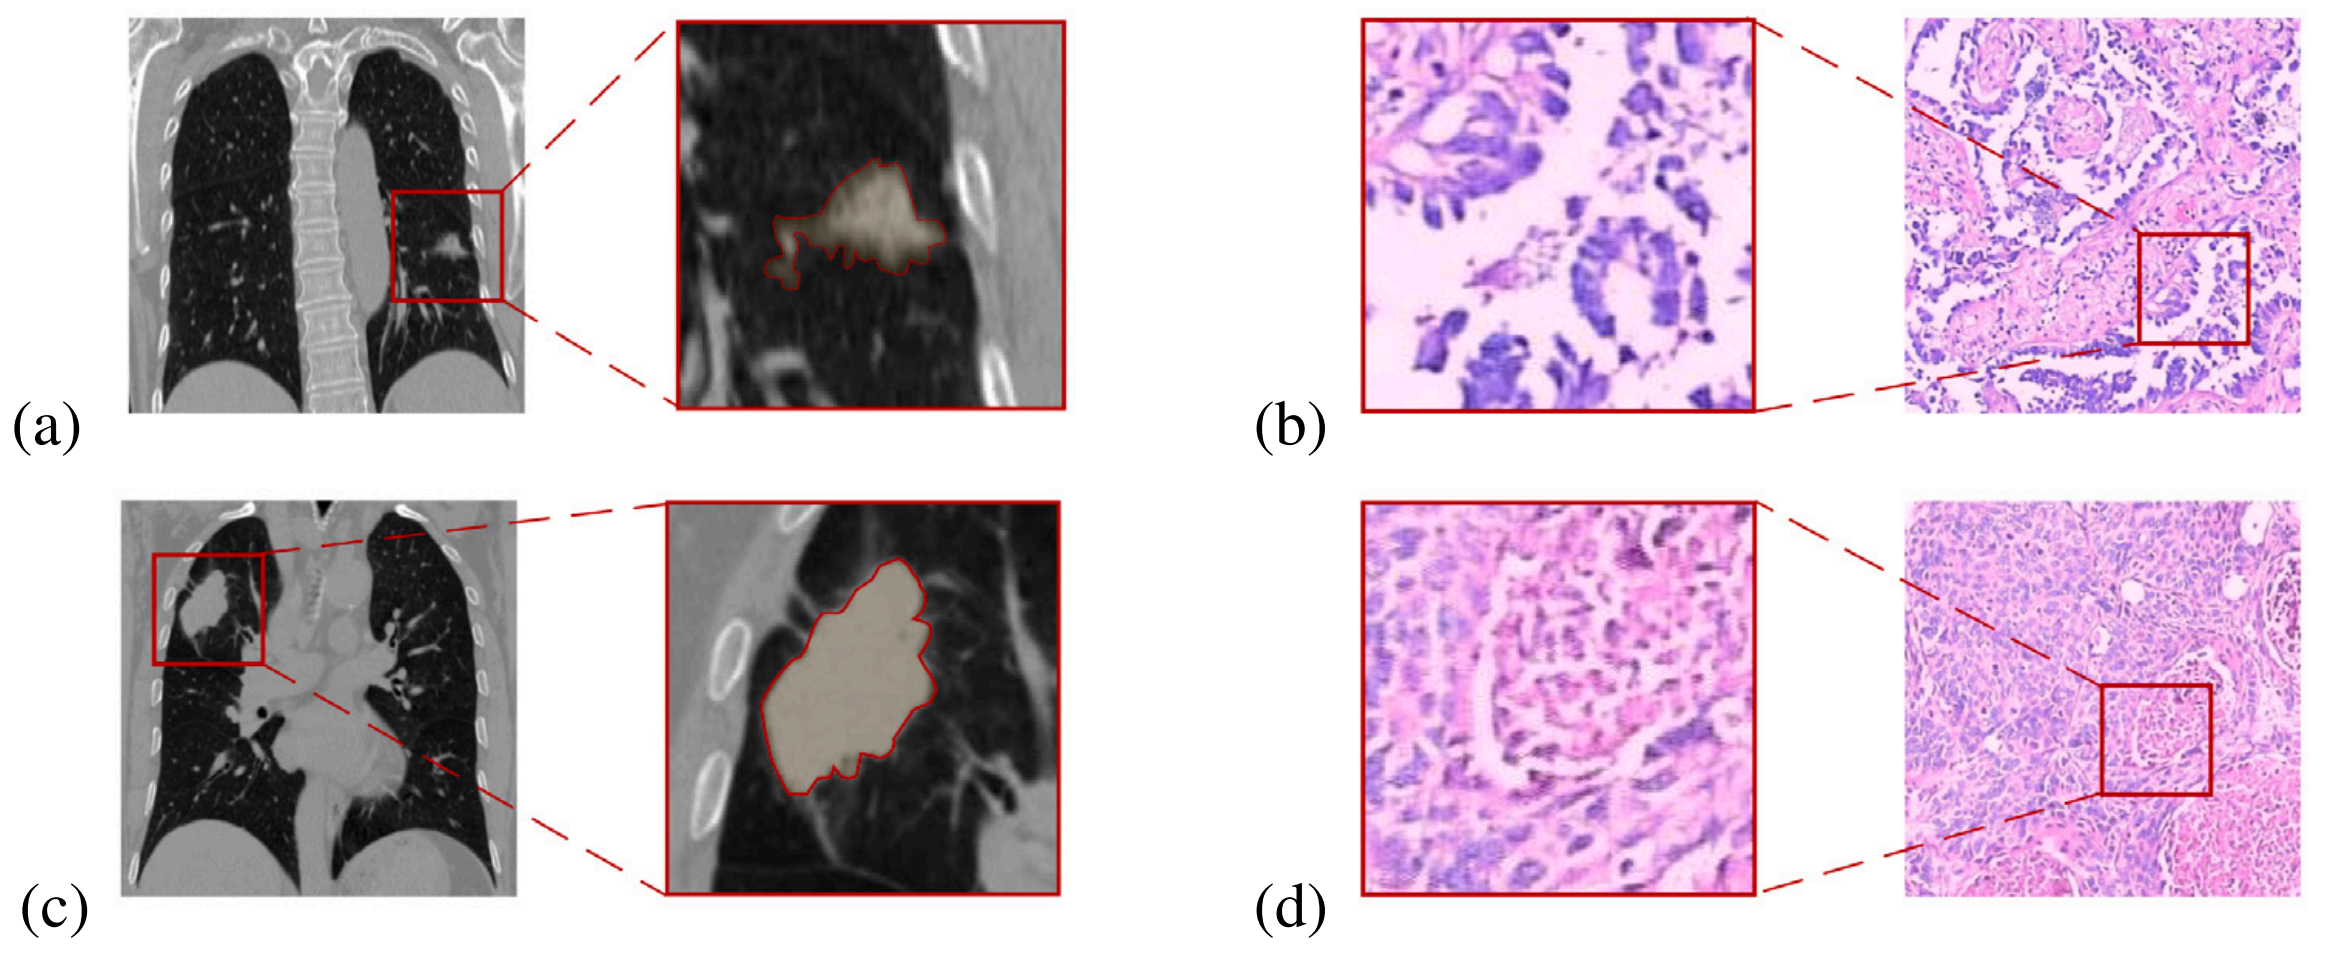

Fig. 1 展示了两组图像:LUAD(肺腺癌)病例的CT图像和病理图像(a和b),以及LUSC(肺鳞癌)病例的CT图像和病理图像(c和d)。

这些图像的详细模式可以帮助识别和区分两种不同类型的肺癌亚型。

LUAD病例(a & b):第一组图像展示了肺腺癌的CT图像(a)和对应的病理图像(b)。CT图像可能显示了肿瘤的大小、形状、位置以及可能的转移情况,而病理图像则提供了细胞形态、细胞分化程度、细胞密度等详细信息。这些信息对于理解肿瘤的生物学行为和制定治疗计划至关重要。

LUSC病例(c & d):第二组图像展示了肺鳞癌的CT图像©和对应的病理图像(d)。与腺癌相比,鳞癌在CT图像上的表现形式可能不同,病理图像也会反映出不同的细胞学特征。例如,鳞癌可能在CT图像上呈现为中央型肿瘤,而病理图像可能显示角化珠的形成,这是鳞癌的一个特征。

Fig. 1的分析表明,通过结合影像学和病理学数据,可以更全面地理解肺癌的特征,并为开发更准确的诊断工具提供支持。